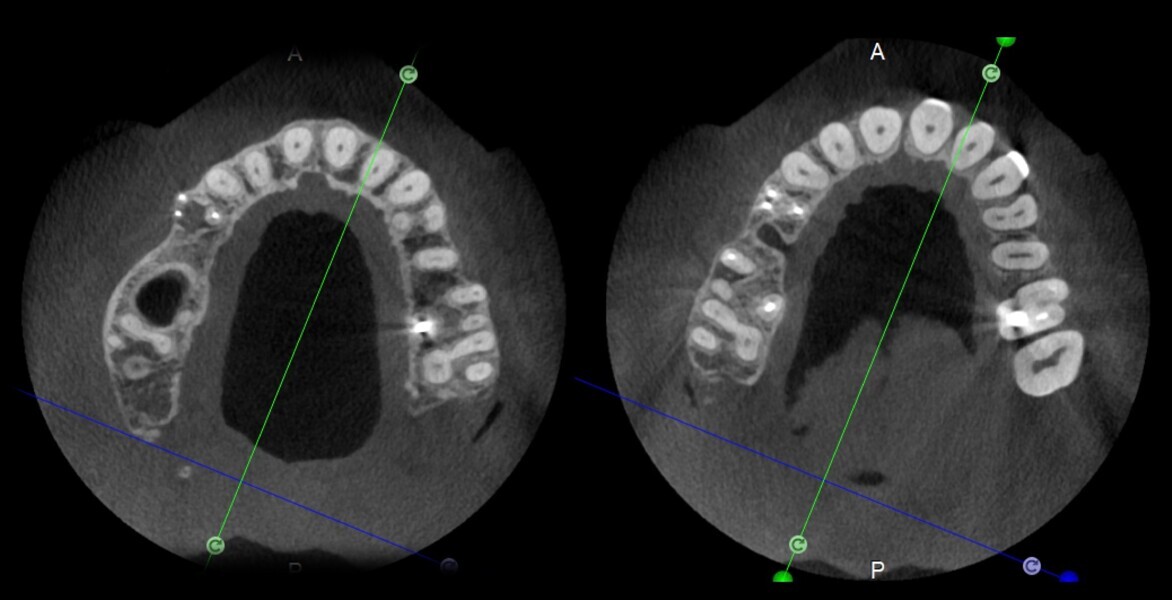

Use of 3D technology in the diagnosis and treatment of endodontic disease